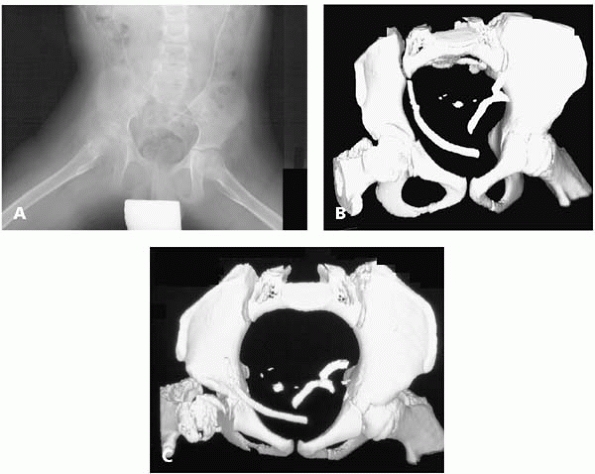

up only about 5% of hip subluxations and dislocations in children with

CP, they can be more difficult to diagnose.13

To stay out of trouble, understand that the radiographs in children

with an anterior hip dislocation can look perfectly normal (Fig. 14-8).

These children do not usually have the classic hip flexion adduction

posture. Instead, they are usually in the figure-of-4 position with

their hip extended, abducted and

externally

rotated. If you feel a prominence in the groin and see this figure-of-4

position and are suspicious for an anterior dislocation, a CT scan of

the pelvis can be very helpful. Remember, in these children the hip is

out the front and the anterior acetabulum may be deficient. A Pemberton

or a Dega osteotomy that focuses on the front of the acetabulum is good

in this population.

![]() |

|

▪ FIGURE 14-8 This AP radiograph (A)

is difficult to interpret—the hips actually look fairly well reduced. The surgeon was suspicious, however, because the child preferred an abducted, extended hip position, and the parents could feel “clunking” with diapering, and sometimes noticed a lump in the groin. The surgeon obtained a CT (B,C), showing anterior hip subluxation. |